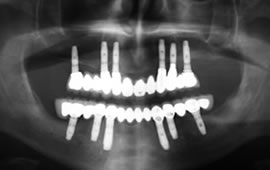

Being able to fabricate an implant retained upper or lower bridge was only a dream a few years back regaining taste and ability to chew without fear are major achievements not to mention being able to maintain teeth as if they were your own. Difficult to phathom but true these days. If you are tired of denture adhesives and wish to explore your possibilities, please do not hesitate to contact us or send your x-rays via email.

See photos of a complete dental implant case